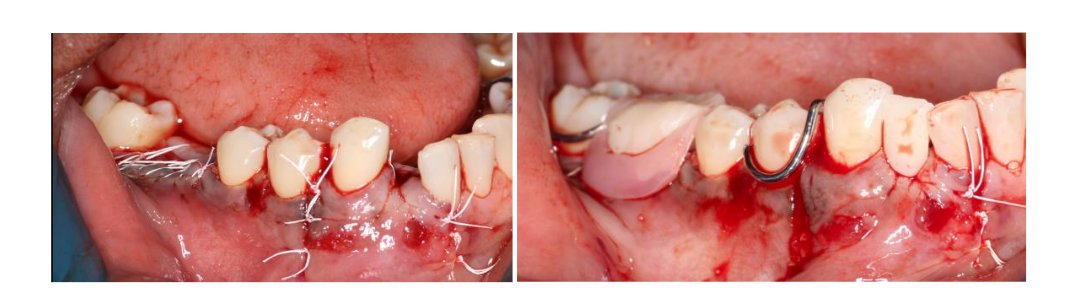

Figure 4. Surgical photos following removal of tooth #26, showing enucleation of a large cyst measuring approximately 18 mm in length and 8 mm in width. Reconstruction of the bony defect performed by the guided bone regeneration along with bioabsorbable membrane, which improved prognosis of the neighboring teeth #25 and 27 in addition to fill in the bony defect of the #26.